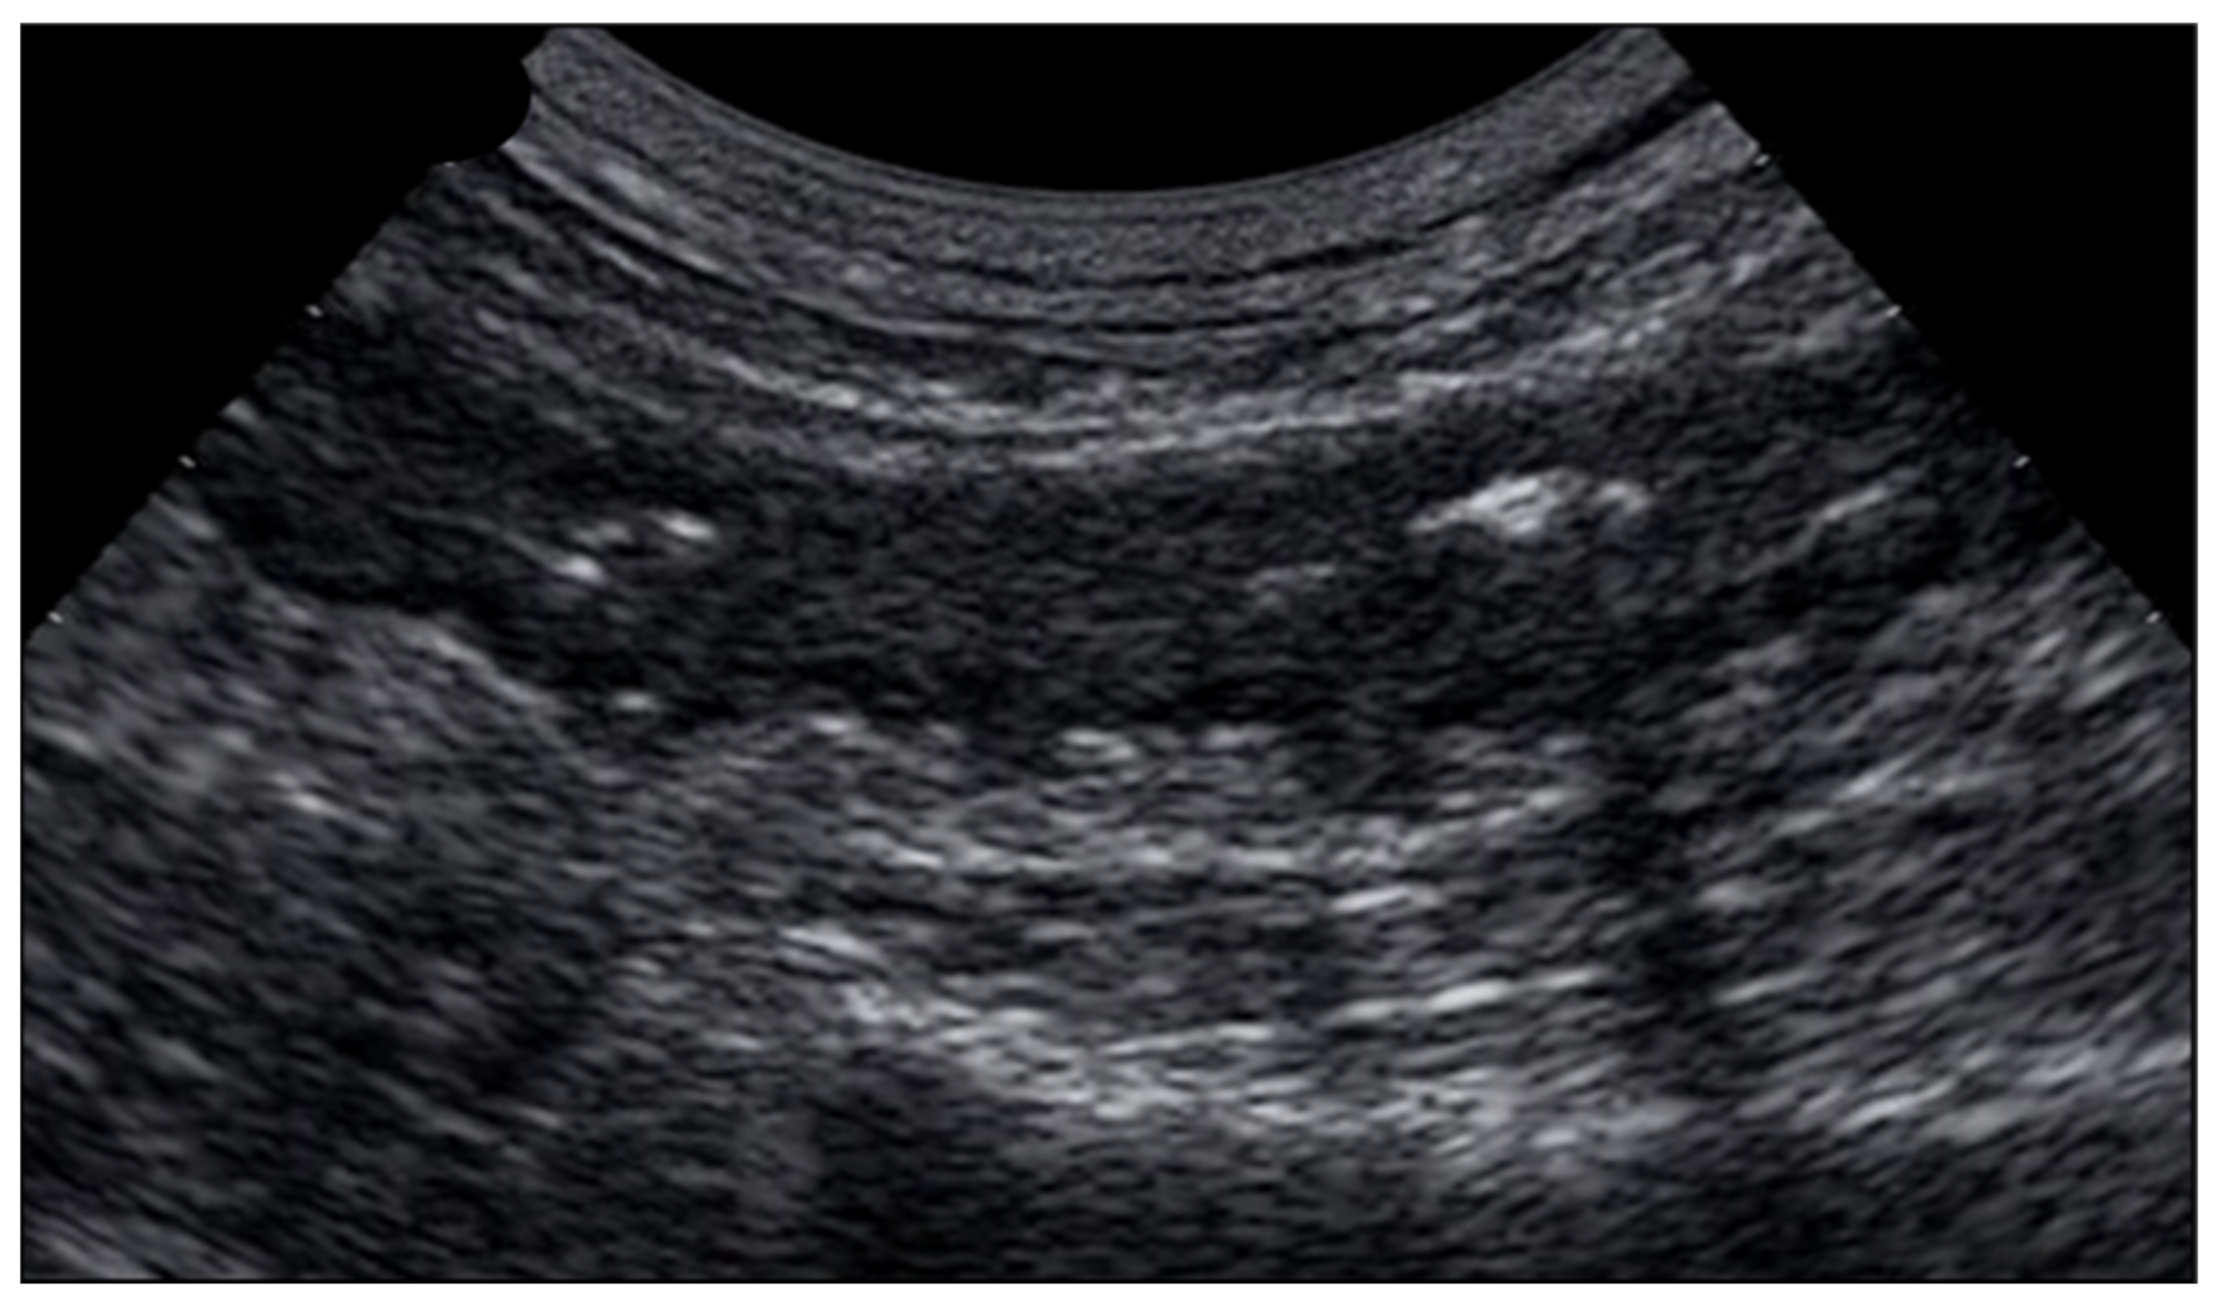

6.1. GIUS Signs of SBO

8.1. Non-Occlusive Mesenteric Ischemia

8.2. Acute Venous Mesenteric Ischemia

8.3. Ischemic Colitis